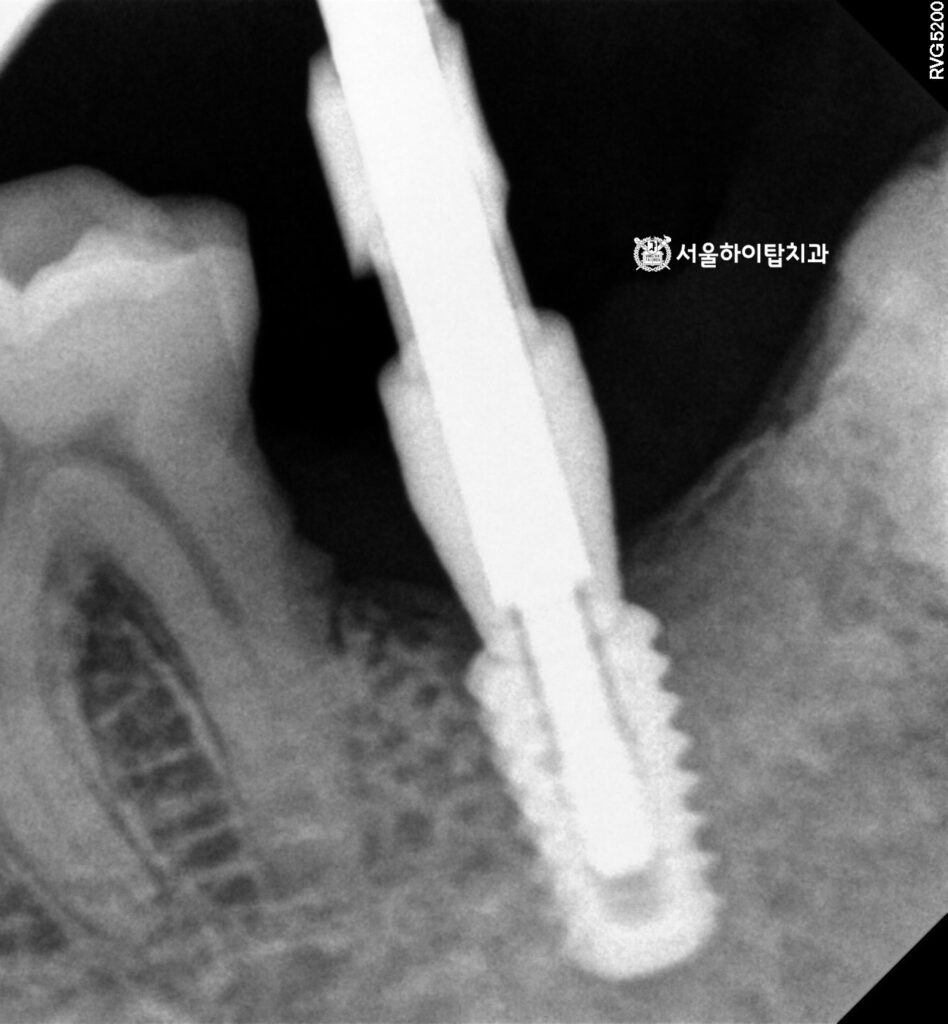

5. 바이트 코핑 체결

골 유착이 충분히 이루어진 후에는

바이트 코핑을 체결하여 실제

교합 상태를 정확히 기록합니다.

이 정보를 바탕으로

환자 맞춤형 보철을 제작하면,

저작 기능과 심미성을 모두 만족시키는

최종 보철을 만들 수 있습니다.